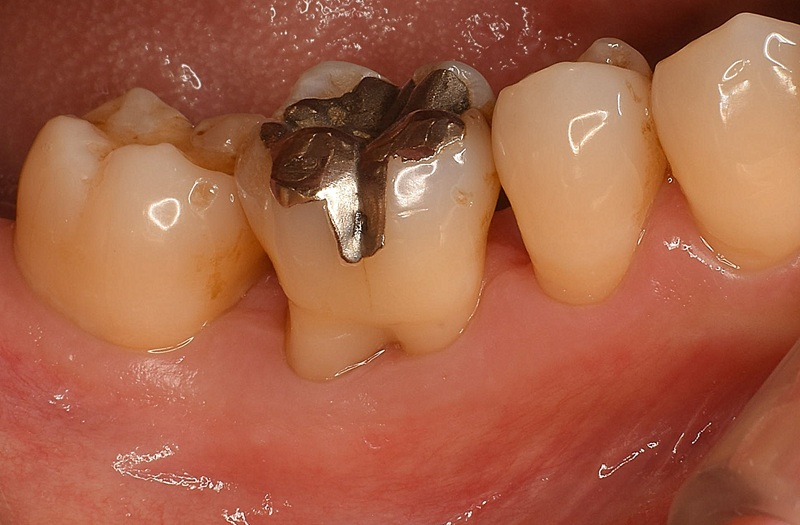

Case2

術前

術中

術後

| 治療名 | 再生療法 |

|---|---|

| 治療説明 | 右下6に重度の歯周病があり、通常の歯周治療でも改善しませんでした。歯周組織再生療法を行い、吸収してしまった骨を再生し、今後の歯周病の進行リスクを減らす事ができました。歯肉退縮もあったため同時に結合組織を移植し、骨と歯肉の再生を同時に行っています。 |

| 治療回数・期間 | 6ヶ月 |

| 副作用とリスク | 手術後に出血、腫脹、疼痛が生じることがあります。手術後は術部の創傷安定のためにブラッシング制限、食事制限があります。手術が複数回となることがあります。 |

| 料金(税込) | 再生療法:165,000円 結合組織移植:55,000円 総額:220,000円 |